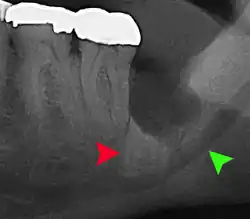

| 3D CT of an impacted wisdom tooth adjacent the inferior alveolar nerve prior to removal of wisdom tooth | |

Coronectomy is a procedure where the crown of the impacted wisdom tooth is removed, but the roots are intentionally left in place. It is indicated when there is no disease of the dental pulp or infection around the crown of the tooth, and there is a high risk of inferior alveolar nerve injury.[36]

Coronectomy, while lessening the immediate risk to the inferior alveolar nerve function has its own complication rates and can result in repeated surgeries. Between 2.3% and 38.3% of roots loosen during the procedure and need to be removed and up to 4.9% of cases require reoperation due to persistent pain, root exposure or persistent infection. The roots have also been reported to migrate in 13.2% to 85.9% of cases.[36]